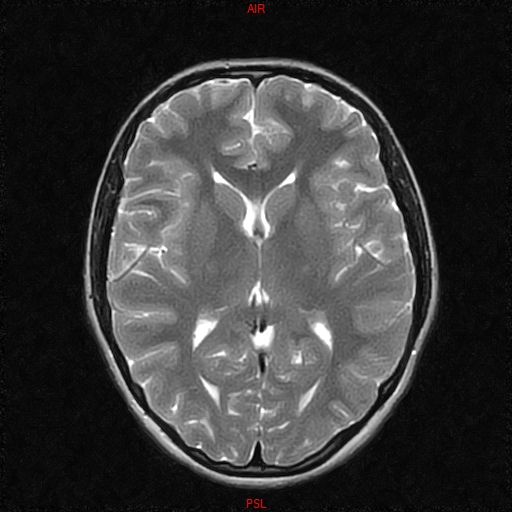

• RESONANCIA NORMAL CRANEAL T2 AXIAL